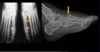

Cisto ósseo simples com fratura

Lesão litica unicameral.

Localização: úmero proximal e femur (< 20 anos) ou calcâneo, talus, ileo (> 20 anos).

Se fratura: Sinal do fragmento caído.